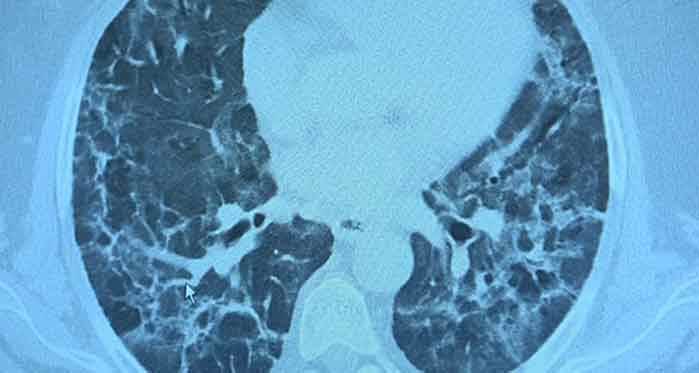

Kliniğe gelen kişilerin akciğer tomografilerine inceleyen Prof. Dr. Özkaya, "62 yaşında bir teyzemiz 11 Mart'ta yoğun bakımda solunum yetmezliği ile hastaneye yattığında hayati tehlikesi vardı ve Covid- 19'u atlattı. Yalnız aradan 3 ay geçmesine rağmen hala akciğerinde Covid - 19'un uzamış etkileri dediğimiz sekel lezyonları var. Bu hasta nefes darlığı çekiyor. Diğer bir vaka örneği verirsek, 62 yaşında bir erkek hasta. Mart'ın sonlarında geldiğinde röntgeninde küçücük buzlu camları vardı. Birden Nisan'ın ilk haftası 10 gün içinde çok yaygın lezyonlar olmaya başladı. Yoğun bakımda takip etmek zorunda kaldık. Bu hastamızın hayatı kurtulduktan sonra filmine baktığımızda yine sekel lezyonlar görüyoruz. Böyle yıpratıcı, harap edici bir klinik tablo ortaya çıkıyor" diye konuştu.